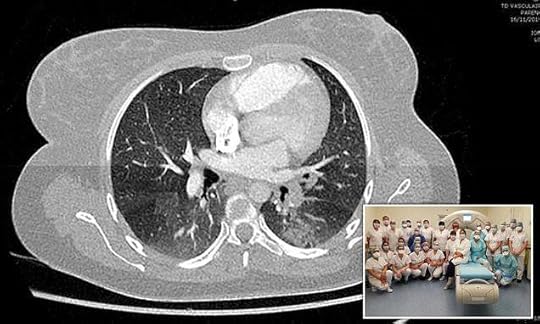

Coronavirus may have been in Europe in NOVEMBER

It was never China #Covid19

Scientists from Colmar, northeastern France, examined almost 2,500 X-rays from late 2019 and were able to identify two scans that presented with the symptoms of Covid-19.